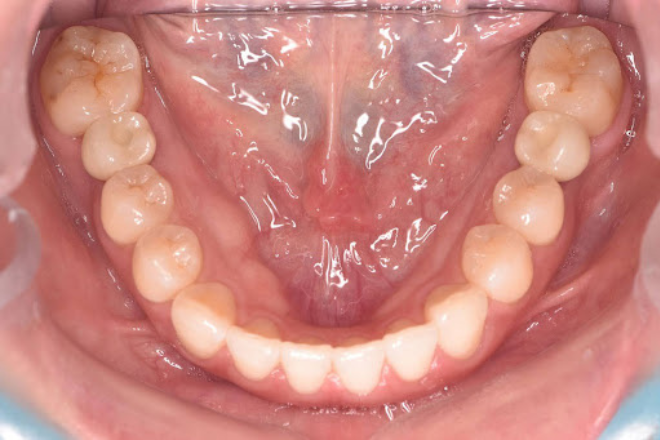

以下は、赤坂さくら歯科クリニックのインプラントでしっかり噛めるようになった症例です。

下顎左右6番を虫歯で失われていたため、サクライナーというオリジナルマウスピース矯正で隙間を埋めて2本のインプラントを埋入しました。

After

術後は良好で旦那様も紹介いただき、ご夫婦で赤坂さくら歯科クリニックでインプラントをされています。